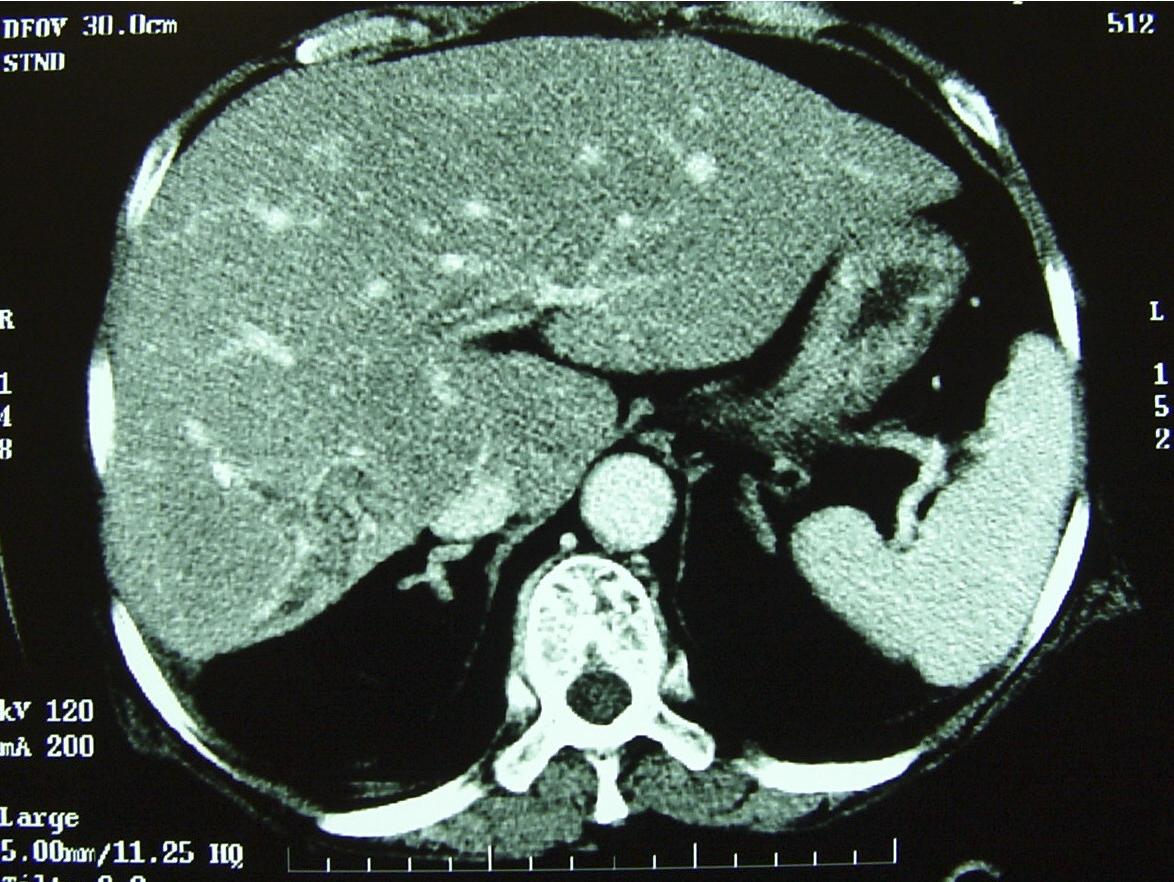

The most common site of the ductal strictures is in the larger branches. Main left-sided ducts are more likely to be involved followed by main right ducts and intrahepatic ducts. Proximal dilatation of biliary structures can be observed if the stricture is severe. Long strictures can occur, but these are usually located in the intrahepatic biliary tree and are manifested by tubular narrowing over a length of duct ( Fig. 44.2 ). Main left duct structures are found in 40% of patients with RPC. The exact reason for this pattern remains unknown, but it is believed that because the left duct is oriented more horizontally, this may result in a more sluggish flow of bile exacerbating stasis and stone formation. The main right hepatic duct is involved in approximately 20% of patients with RPC. The remaining 40% of patients have bilateral involvement or intrahepatic ductal involvement ( Fig. 44.3 ).

FIGURE 44.2, A, Dilatation of left intrahepatic ducts with multiple stones inside the biliary tree. There is evidence of portal hypertension with splenomegaly and varices formation (see Chapter 16 ). B, Endoscopic retrograde cholangiopancreatography showing stone in common bile duct and absence of S2 duct in the left biliary system, which is suggestive of a stricture or biliary stone impaction in the S2 duct. Liver resection is indicated for infection control and removal of a possibly stenotic biliary segment, which is potentially malignant (see Chapter 30 ). C, Left hepatectomy performed. The left biliary duct was packed with pigmented stones.